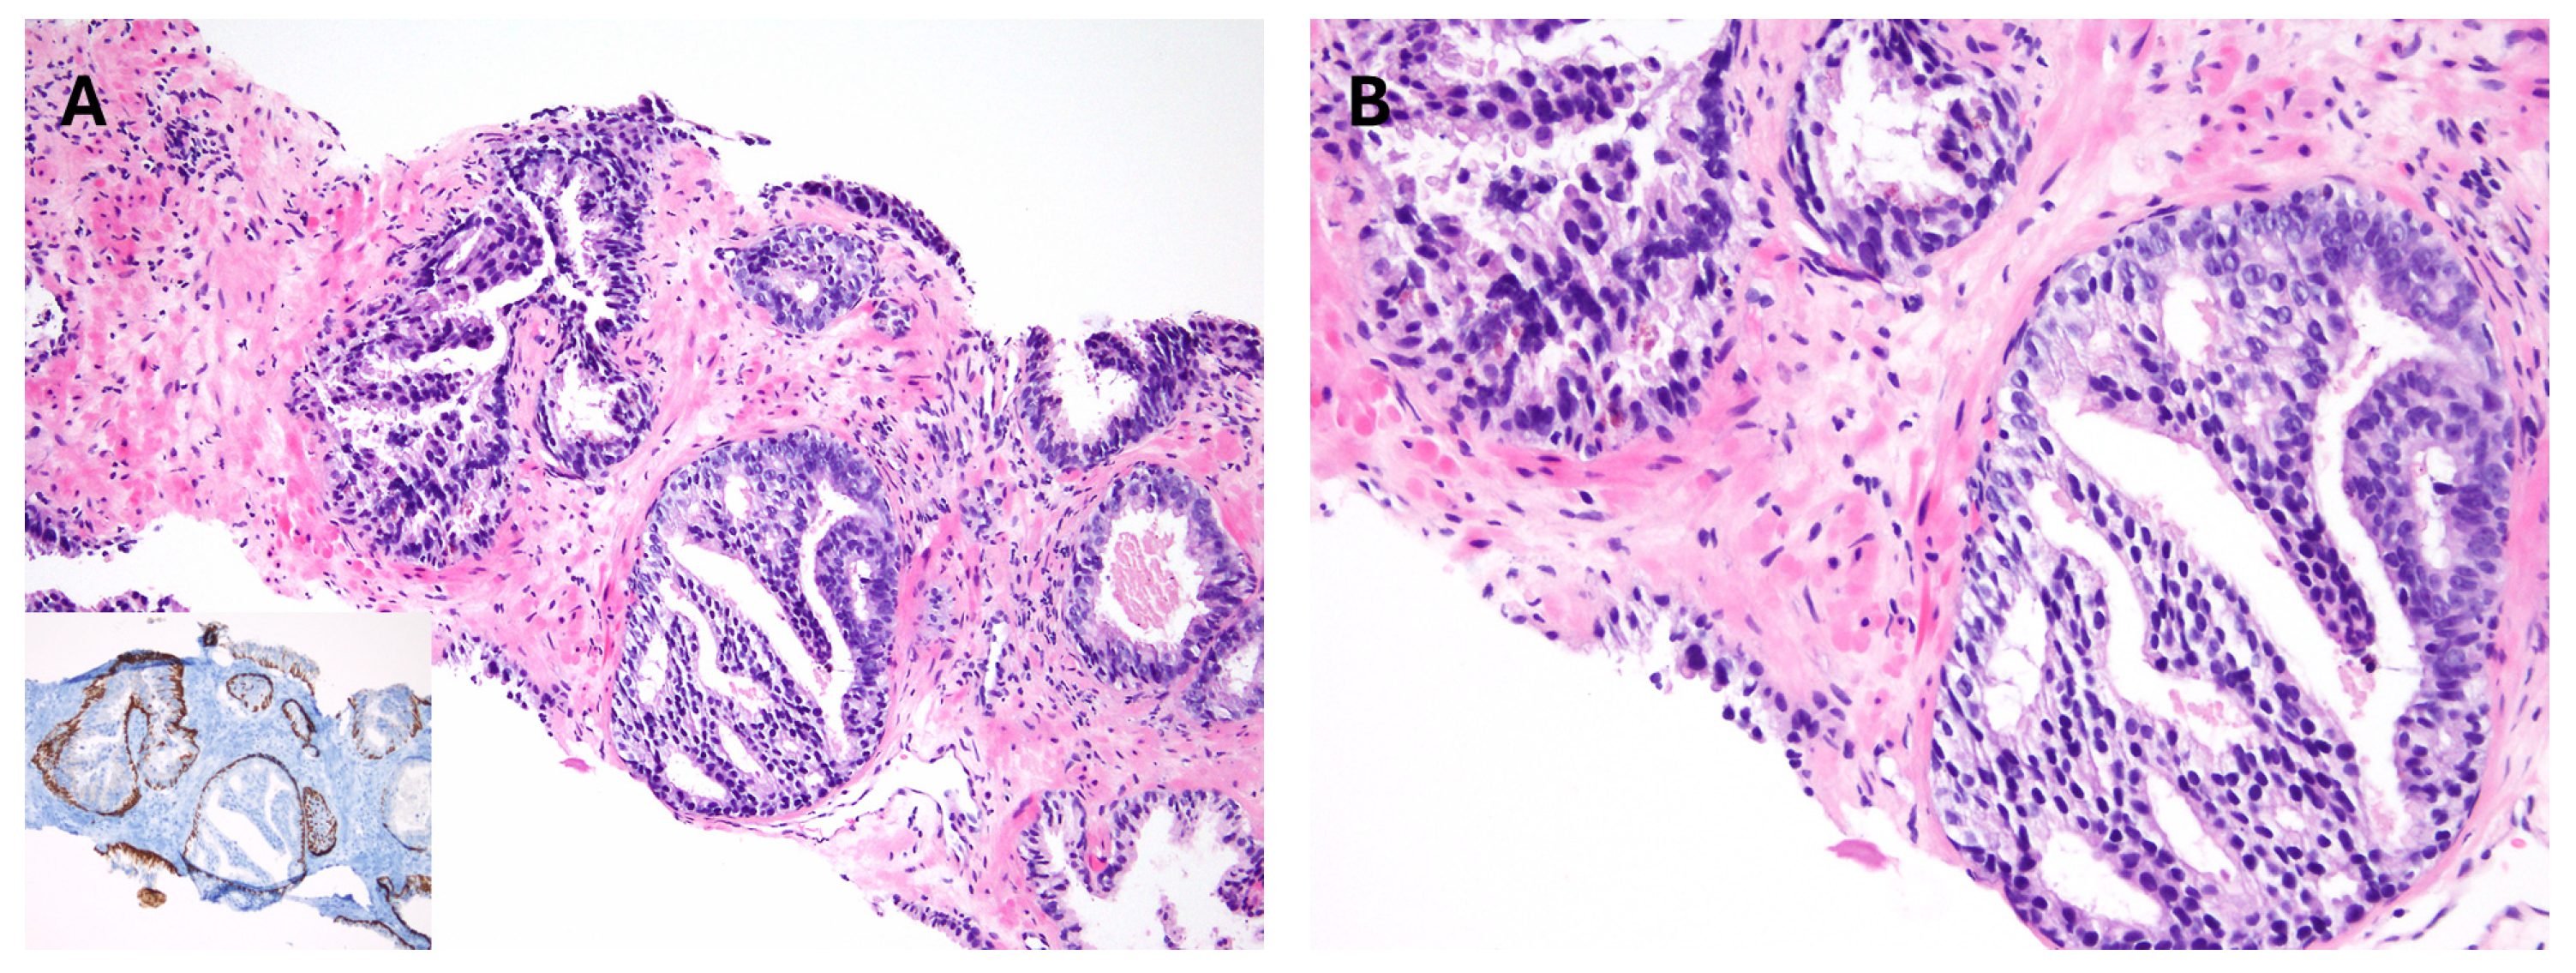

3.3. Modern Gleason Grading Rules

7. Intraductal Carcinoma

8. Atypical Intraductal Proliferation